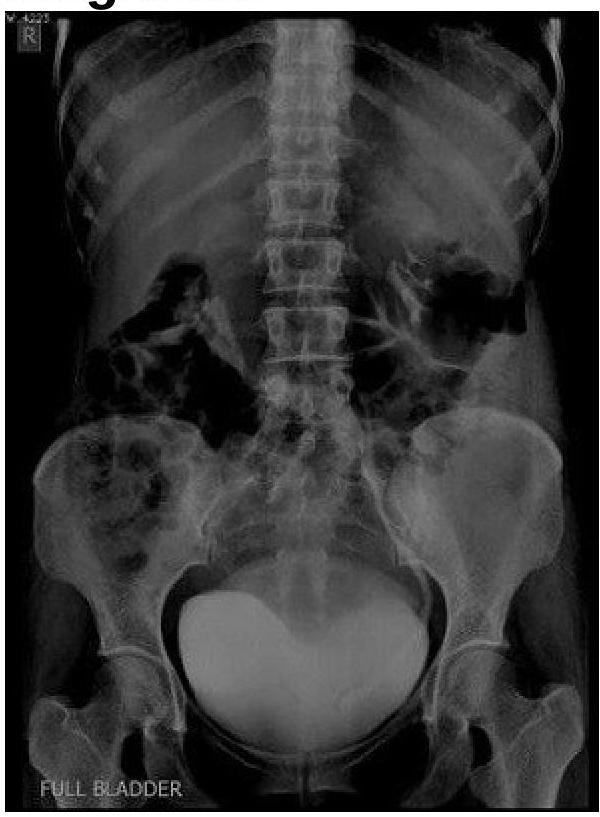

A female patient presented with recurrent urinary tract infections. What is the most probable diagnosis based on the imaging findings?

Explanation: ***Ureterocele*** - The imaging shows a rounded, radiolucent filling defect within the **contrast-filled bladder**, which is characteristic of a **ureterocele**. This is often associated with recurrent UTIs due to obstruction and stasis. - A ureterocele is a **congenital dilation** of the terminal part of the ureter as it enters the bladder, causing a cystic protrusion into the bladder lumen. *Congenital megaureter* - A congenital megaureter would appear as a **diffusely dilated ureter** throughout its course, often extending from the renal pelvis, rather than a localized cystic structure within the bladder. - While it can cause recurrent UTIs, the specific bladder filling defect seen here is not typical for an isolated megaureter. *Urinary stones* - Urinary stones would typically appear as **radiopaque foci** of varying size, depending on their composition, within the collecting system or bladder. - They do not typically present as a smooth, rounded filling defect within a contrast-filled bladder. *Ureteral duplication* - Ureteral duplication involves two separate ureters draining a single kidney, which often have their own separate openings into the bladder or meet before entering. - While it can be associated with UTIs (especially with reflux or ectopia), the primary finding on imaging would be the presence of **two distinct ureters**, not an intravesical cystic structure.